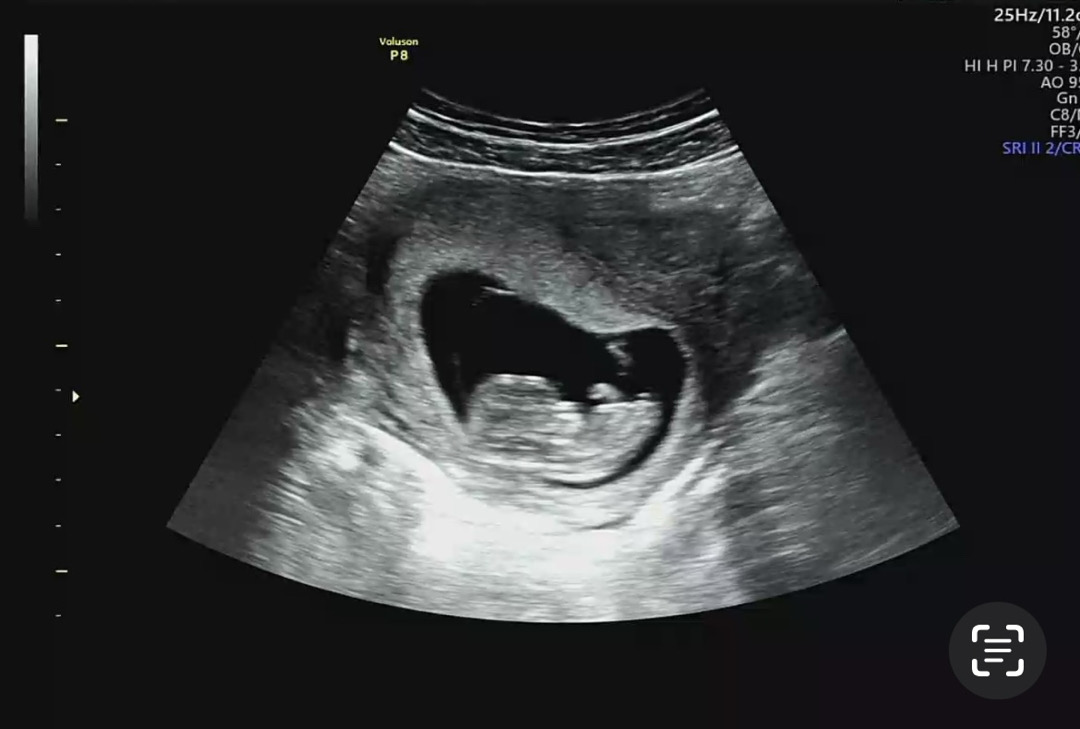

각도법 궁금해요 👶💕

아직 잘 안보이는것 같긴한데 각도법으로 어때 보이시나용!!